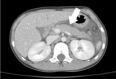

Primary hyperparathyroidism (PHPT) is a hypercalcemia disorder with inappropriately normal or increased serum parathyroid hormone (PTH) levels resulting from excessive secretion of PTH from one or more of the parathyroid glands. PHPT is uncommon in infants and children, with an estimated incidence of 2-5 cases per 100,000 persons. Patients with PHPT usually present with bone pain, urolithiasis, or nephrolithiasis, as well as nonspecific symptoms such as fatigue and weakness. Asymptomatic hypercalcemia may also be detected incidentally. Only a few cases of pediatric PHPT have been reported in Korea. We present three patients (a 9-year-old girl, a 14-year-old boy, and a 14-year-old girl) with PHPT who manifested variable clinical features of hypercalcemia. The first and second patients each had a parathyroid adenoma and presented with abdominal pain caused by pancreatitis and a ureter stone, respectively. The third patient had an ectopic mediastinal parathyroid adenoma and presented with gait disturbance and weakness of the lower extremities. All of the patients underwent surgical resection of parathyroid adenoma, and their serum calcium levels subsequently normalized without medication.